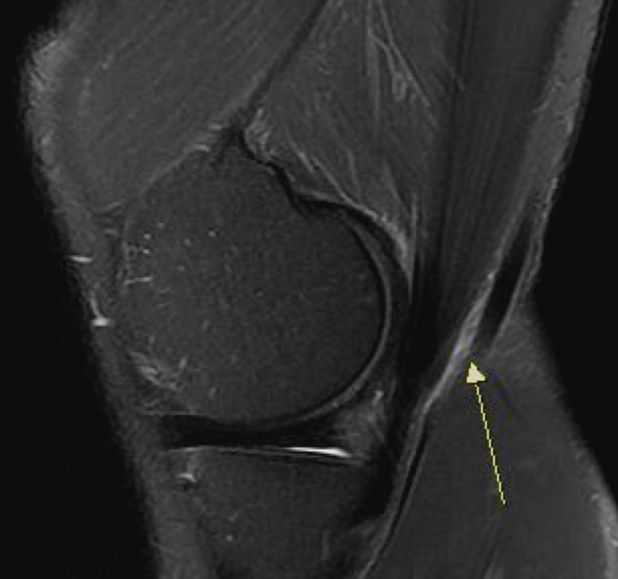

평소 하루 2만보 가까이 걷기를 즐겨하며 지내던 중 갯바위 바다낚시에서 불편한 자세로 종일 서 있었는데 그.후에 양 무릎이 불편하기 시작했습니다. 엑스레이 초음파에선 이상 없었고 오른쪽 MRI 찍어보니 연골판 바깥쪽 붓기와 더불어 근위 경골 관절에 물참/슬개건에 미세한 음영변화/내측.거위발건 염증/연골 찢어짐 없음 으로 판정 받았습니다..쪼그려 앉기 통증. 계단 무리하면 한번씩 통증. 의자에 앉아 있을때 불편감등 연골연화증 증세가 있습니다. 연화증이 맏을까요? 맞다면 어떤 치료를 해야할까요..쉬면서 근육 키우는 수밖에 없나요

• 2번 째 사진

영상소견과 증상을 종합적으로 고려했을 때 연화증이 의심되는 상태가 맞습니다.